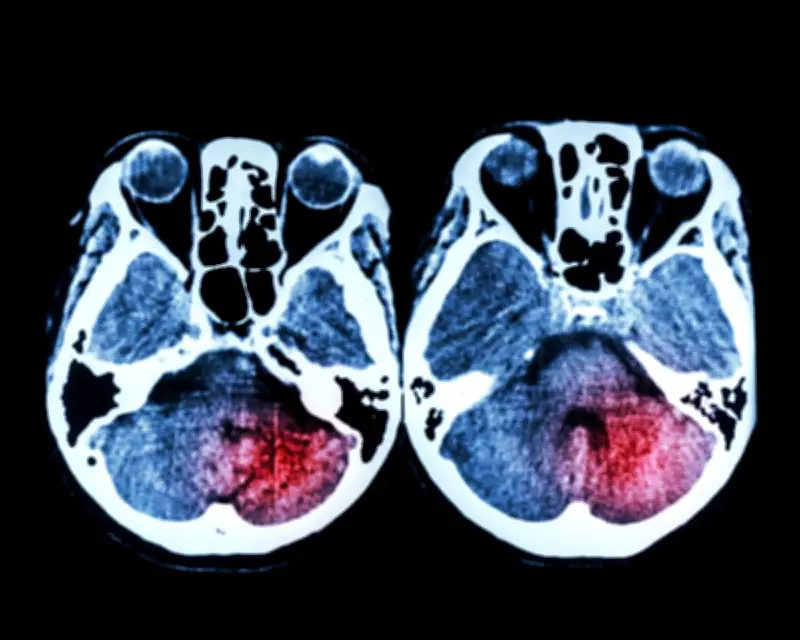

Mechanical thrombectomy, hailed by doctors as a game-changing intervention, involves removing clots from brain arteries to prevent severe disability if administered promptly. The health service was expected to make this procedure available 24/7 nationwide starting April 1, but seven out of England's 24 regional stroke centres have not met this deadline. These centres, located in Hull, Middlesbrough, Leeds, Sheffield, Newcastle, Brighton, and Coventry, primarily cite shortages of doctors and specialized staff as the barrier.

The NHS spends over £100 million annually on thrombectomy, viewing it as a key strategy to reduce the 113,000 avoidable deaths from major conditions like heart disease and cancer in England. Thrombectomy is a minimally invasive procedure where doctors use a catheter to remove brain clots, restoring blood flow. However, without consistent 24/7 access, delays could compromise patient outcomes.